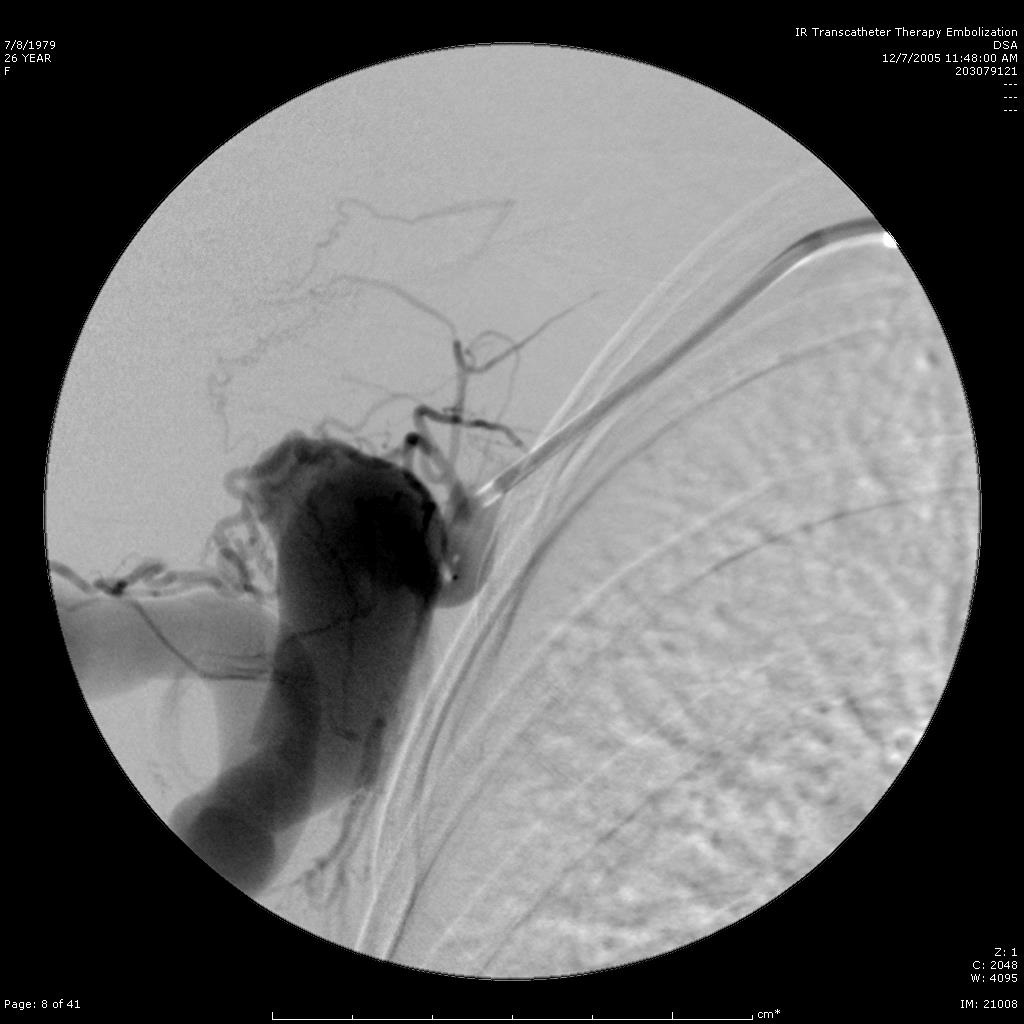

肺动静脉瘘 |

静脉引流 |

动静脉瘘栓塞原则阻塞静脉段 |

静脉段血流速度快,弹簧栓子释放容易远端移位 |

可脱弹簧栓子确保弹簧栓子稳定在静脉段 |

术后造影 |